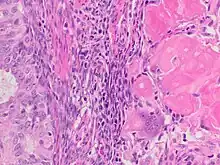

Endometrial adenocarcinoma with necrotic ghost cells of keratinocytes at right in image, leaving pink keratin and clear spaces at the prior locations of the nuclei.

A ghost cell is an enlarged eosinophilic epithelial cell with eosinophilic cytoplasm but without a nucleus.

The ghost cells indicate coagulative necrosis where there is cell death but retainment of cellular architecture. In histologic sections ghost cells are those which appear as shadow cells. They are dead cells. For example, in peripheral blood smear preparations, the RBCs are lysed and appear as ghost cells.